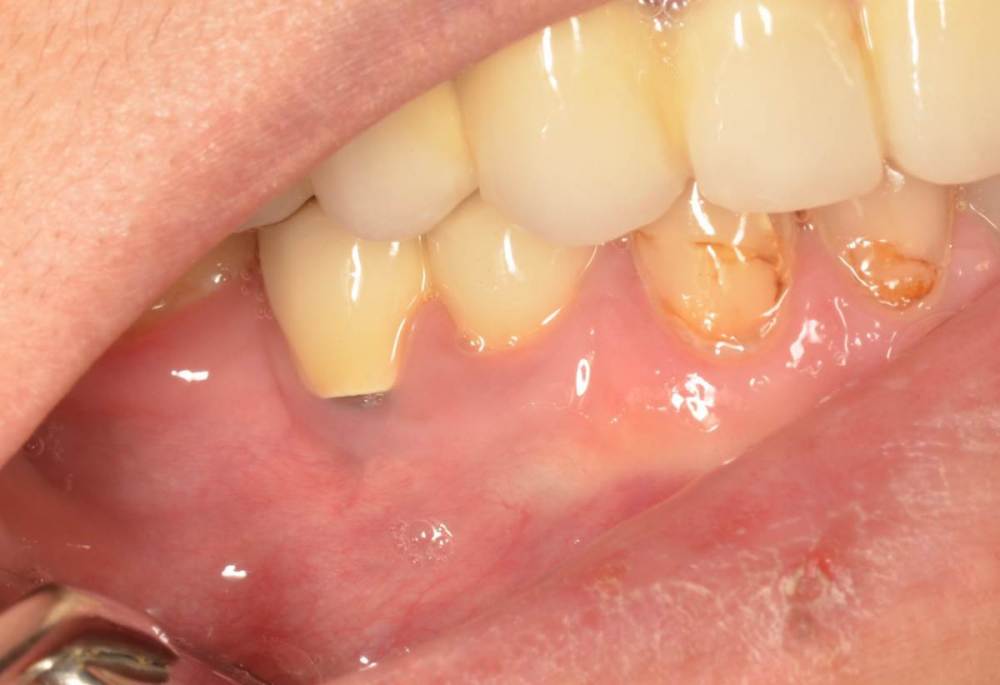

Большой Зеленый Опубликовано 27 мая, 2022 Поделиться Опубликовано 27 мая, 2022 Через 9 лет. Есть немного рецессии.. 2 Ссылка на комментарий

pit Опубликовано 27 мая, 2022 Поделиться Опубликовано 27 мая, 2022 4 часа назад, Большой Зеленый сказал: Через 9 лет. Есть немного рецессии.. Это связано исключительно с вестибулярной позицией импланта. Это как раз к вопросу про те минимальные 2мм до вестиболярной стенки, вне зависимости есть она или ты ее создаешь. Ссылка на комментарий

Большой Зеленый Опубликовано 27 мая, 2022 Поделиться Опубликовано 27 мая, 2022 4 часа назад, pit сказал: Это связано исключительно с вестибулярной позицией импланта. Это как раз к вопросу про те минимальные 2мм до вестиболярной стенки, вне зависимости есть она или ты ее создаешь. С тех пор я стал хитрее умнее и опытнее ))) 1 час назад, alboard сказал: А в чем смысл ее сохранности, если препарируя под имплантат вы все равно ее в большинстве случаев сносите? Первичная стабильность импланта зачастую достигается только перегородкой.. Ссылка на комментарий

Большой Зеленый Опубликовано 28 мая, 2022 Поделиться Опубликовано 28 мая, 2022 12 часов назад, Женька сказал: @Большой Зеленый это вроде ваш старый кейс? напомните пожалуйста, тут присыпка+мембранинг вестибулярно и вестибулярным лоскутом слегка послабленным всё закрыли? Да все так и есть как Вы и описали. Работе почти 10 лет. Присыпка мп3 от остеобила сверху "ильгамовская" губка . Считаю что результат вполне удовлетворительный. Рецессия обусловлена как уже сказали выше вестибулярным положением импланта ,ну и недозаглублен чуток. Ссылка на комментарий